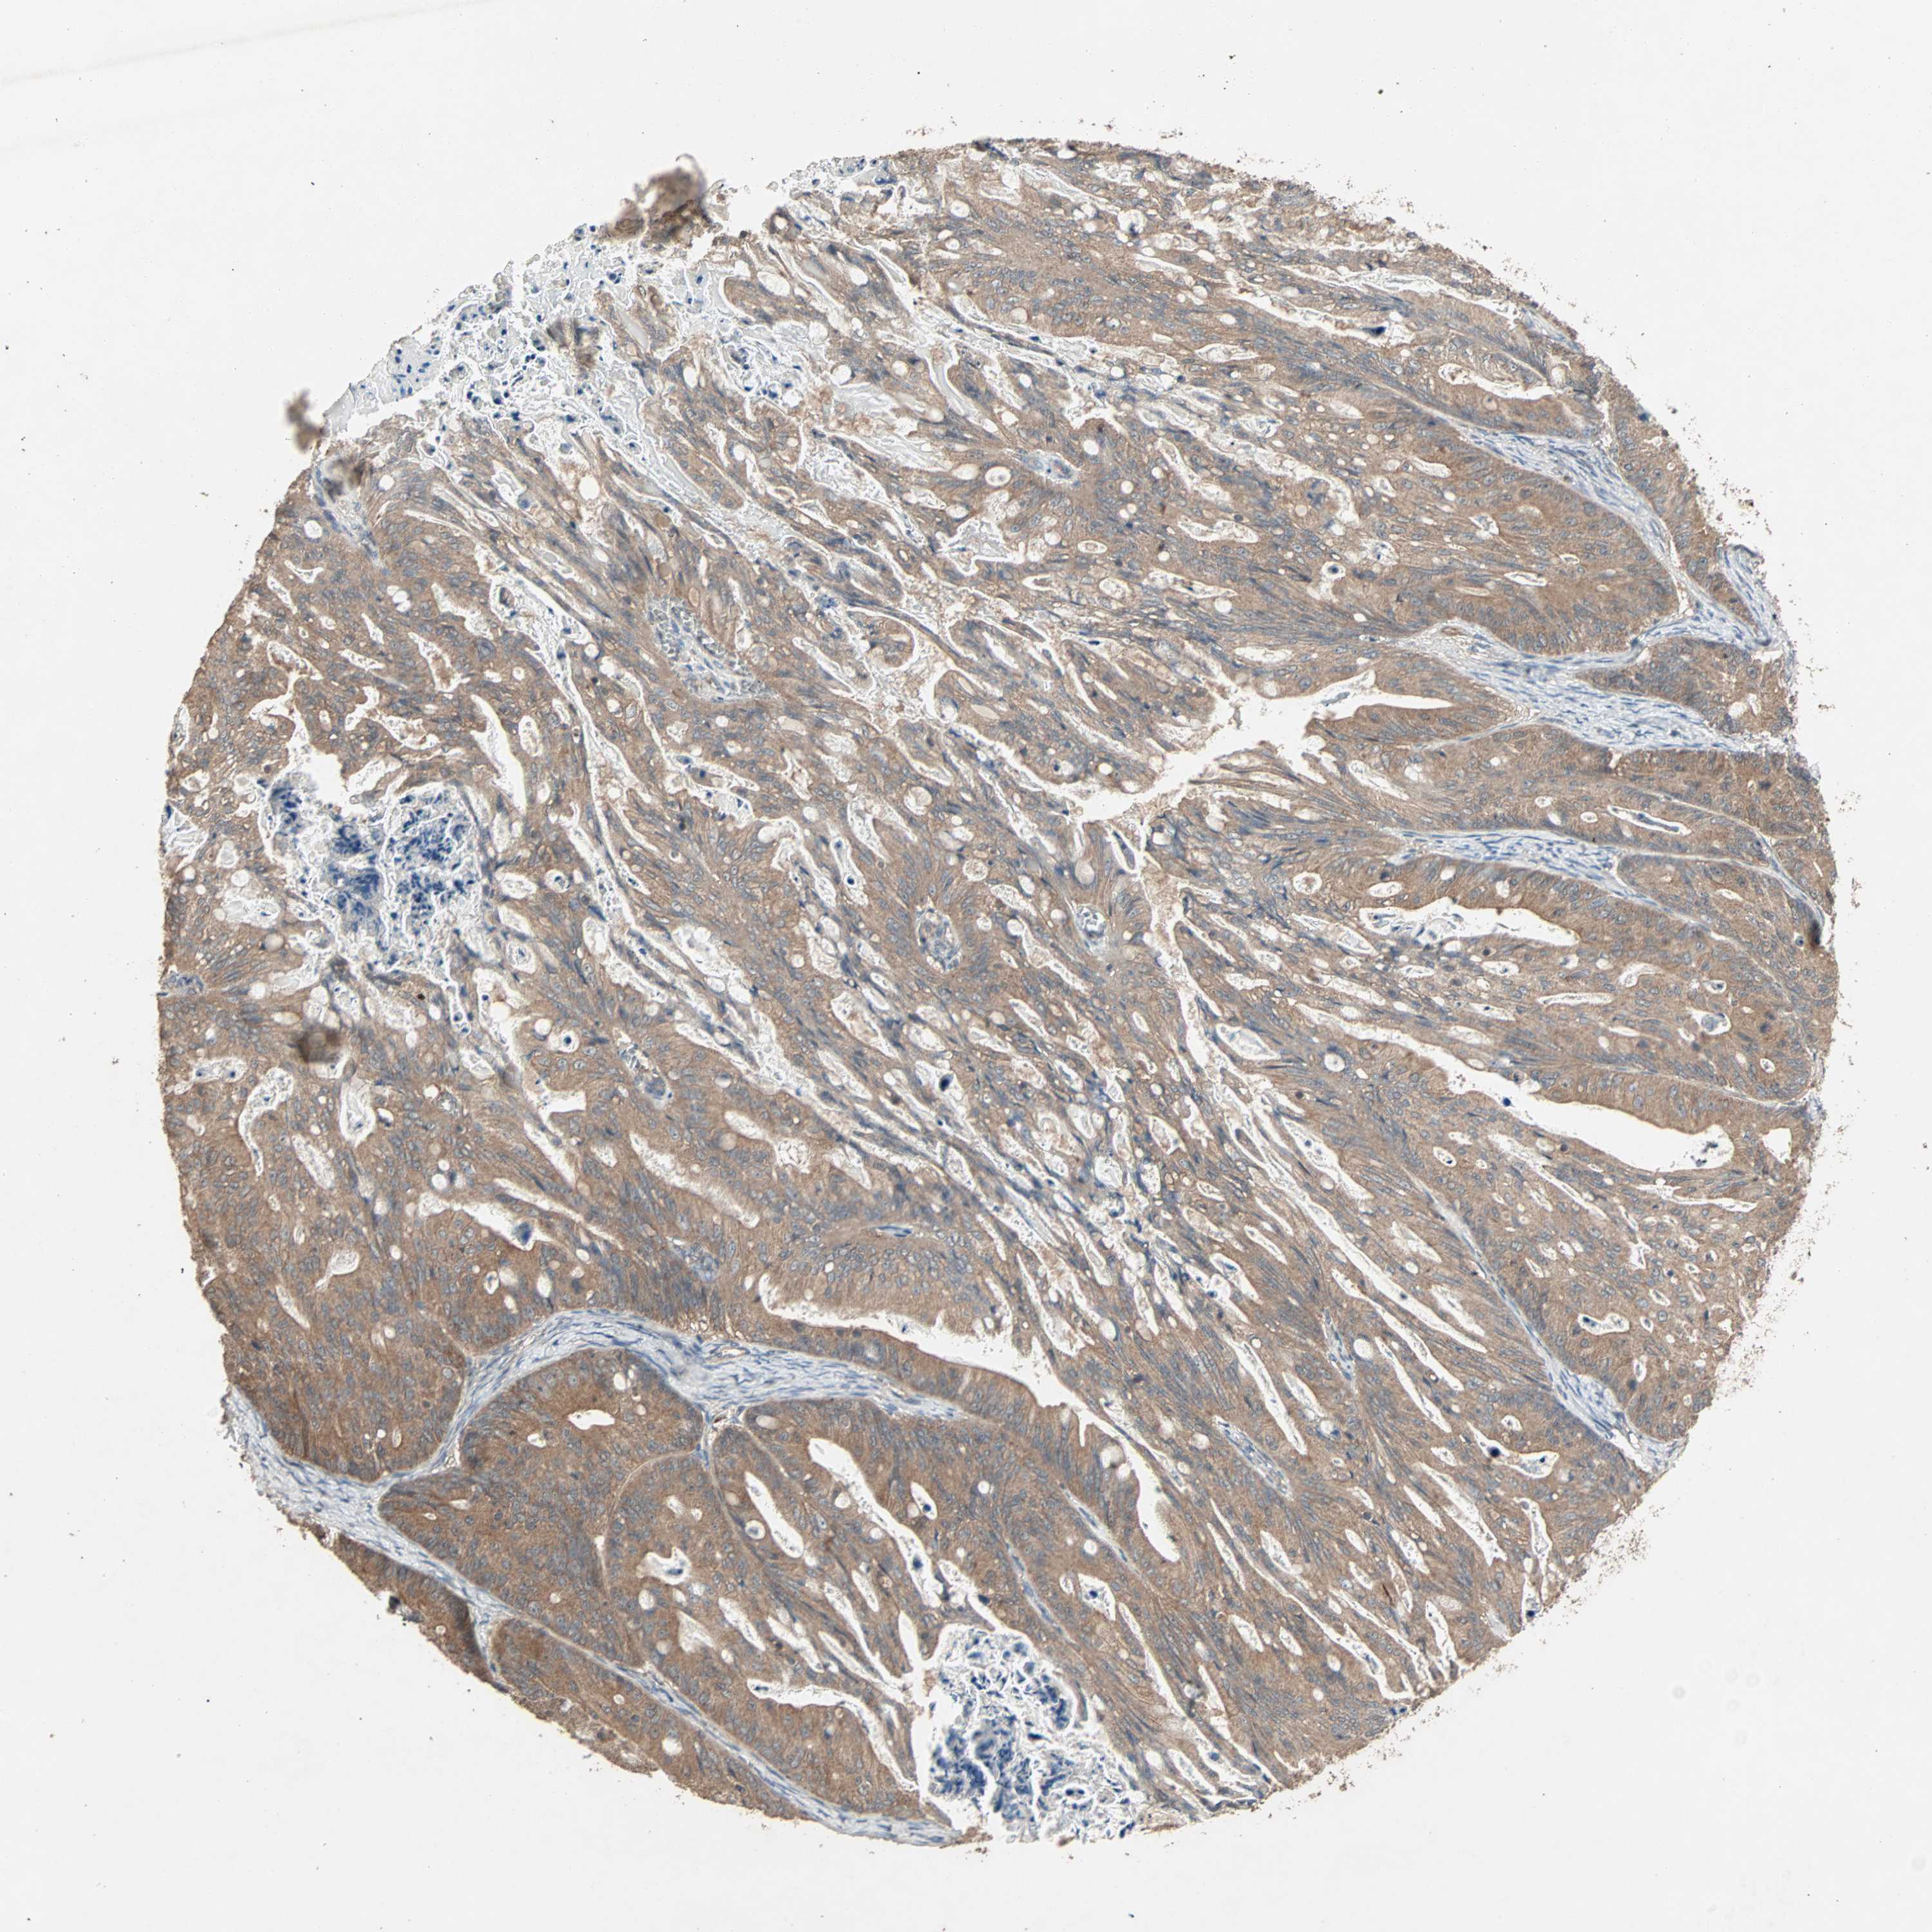

OVARIAN CANCER - Protein expressioni

A mouse-over function shows sample information and annotation data. Click on an image to view it in a full screen mode. Samples can be filtered based on level of antibody staining by selecting one or several of the following categories: high, medium, low and not detected. The assay and annotation is described here.

Note that samples used for immunohistochemistry by the Human Protein Atlas do not correspond to samples in the TCGA dataset.

Antibody stainingi

Antibody staining in the annotated cell types in the current human tissue is reported as not detected, low, medium, or high, based on conventional immunohistochemistry profiling in selected tissues. This score is based on the combination of the staining intensity and fraction of stained cells.

Each image is clickable and will lead to virtual microscopy that enables deeper exploration of all samples and also displays staining intensity scores, fraction scores and subcellular localization as well as patient and tissue information for each sample.

Antibody HPA005651

Staining

High

Medium

Low

Not detected

Intensity

Strong

Moderate

Weak

Negative

Quantity

>75%

75%-25%

<25%

None

Location

Nuclear

Cytoplasmic/membranous

Cytoplasmic/membranous,nuclear

Cystadenocarcinoma, serous, NOS

Carcinoma, endometroid

Cystadenocarcinoma, mucinous, NOS

Carcinoma, NOS